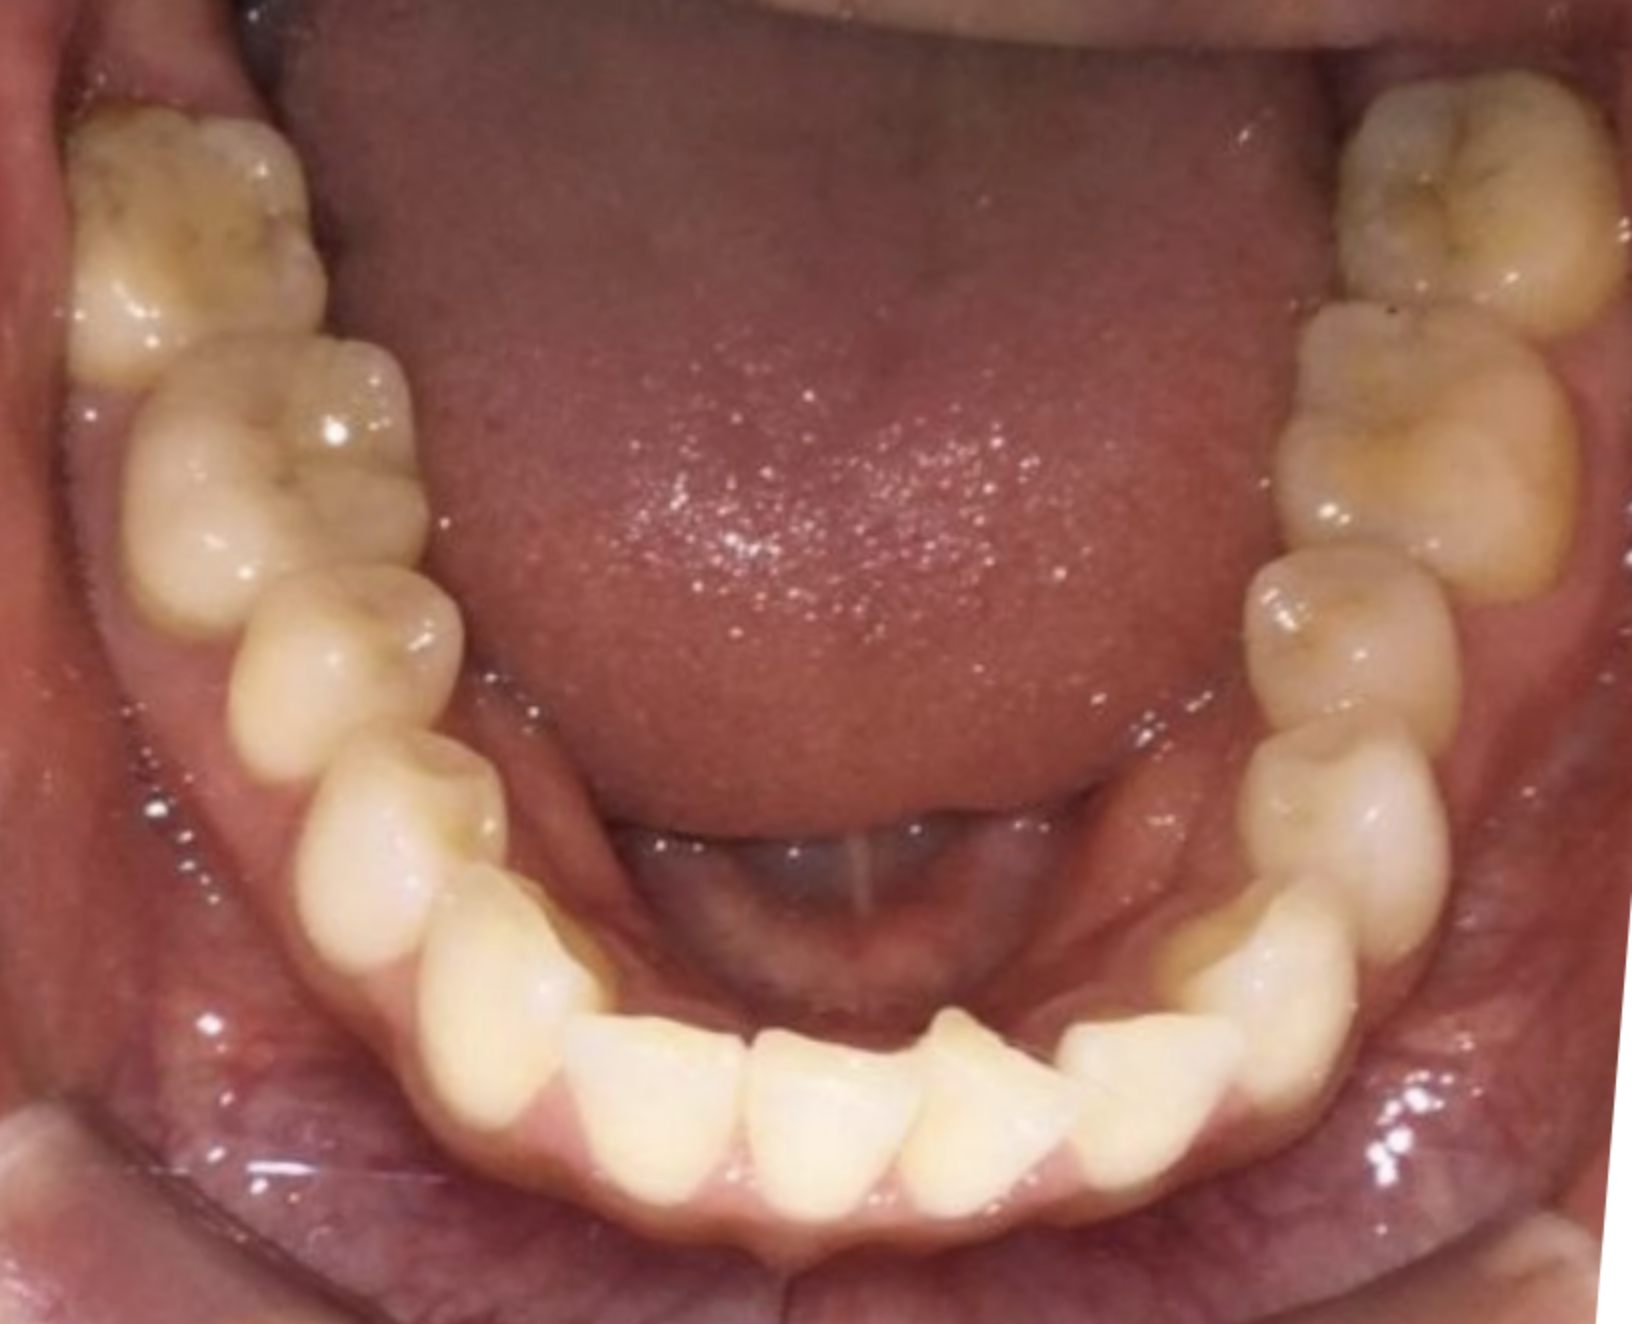

上顎前突のケースを、非抜歯の遠心移動を主体に改善しました。もともと大きく前にでているケースではなかったですが、満足されるところまで時間をかけて丁寧に移動を行いました。

治療後の口腔写真

Before

After